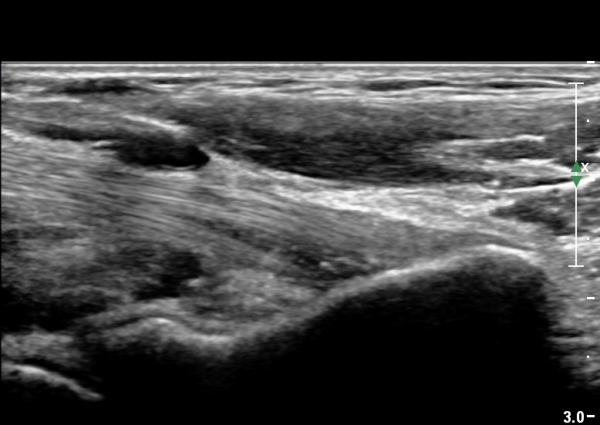

¿ìÃø ÆÈ²ÞÄ¡ ¾ÕÂÊ¿¡¼­ ÀÌµÎ¹Ú±Ù°Ç È¾´Ü¸é°Ë»ç¿¡¼­ À̵ιڱٰǿ¡ ƯÀÌ ¼Ò°ßÀ» º¸ÀÌÁö ¾Ê(±×¸² 1, 2).